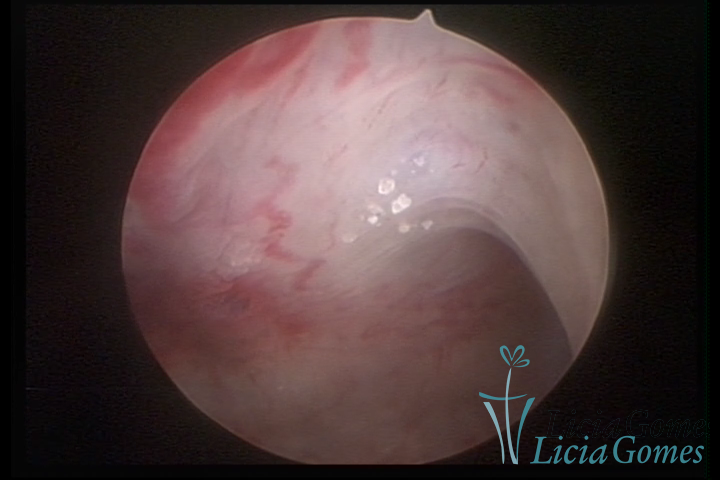

Metaplasia óssea: pontilhado esbranquiçado com calcificações

Metaplasia óssea e lesão de adenomiose